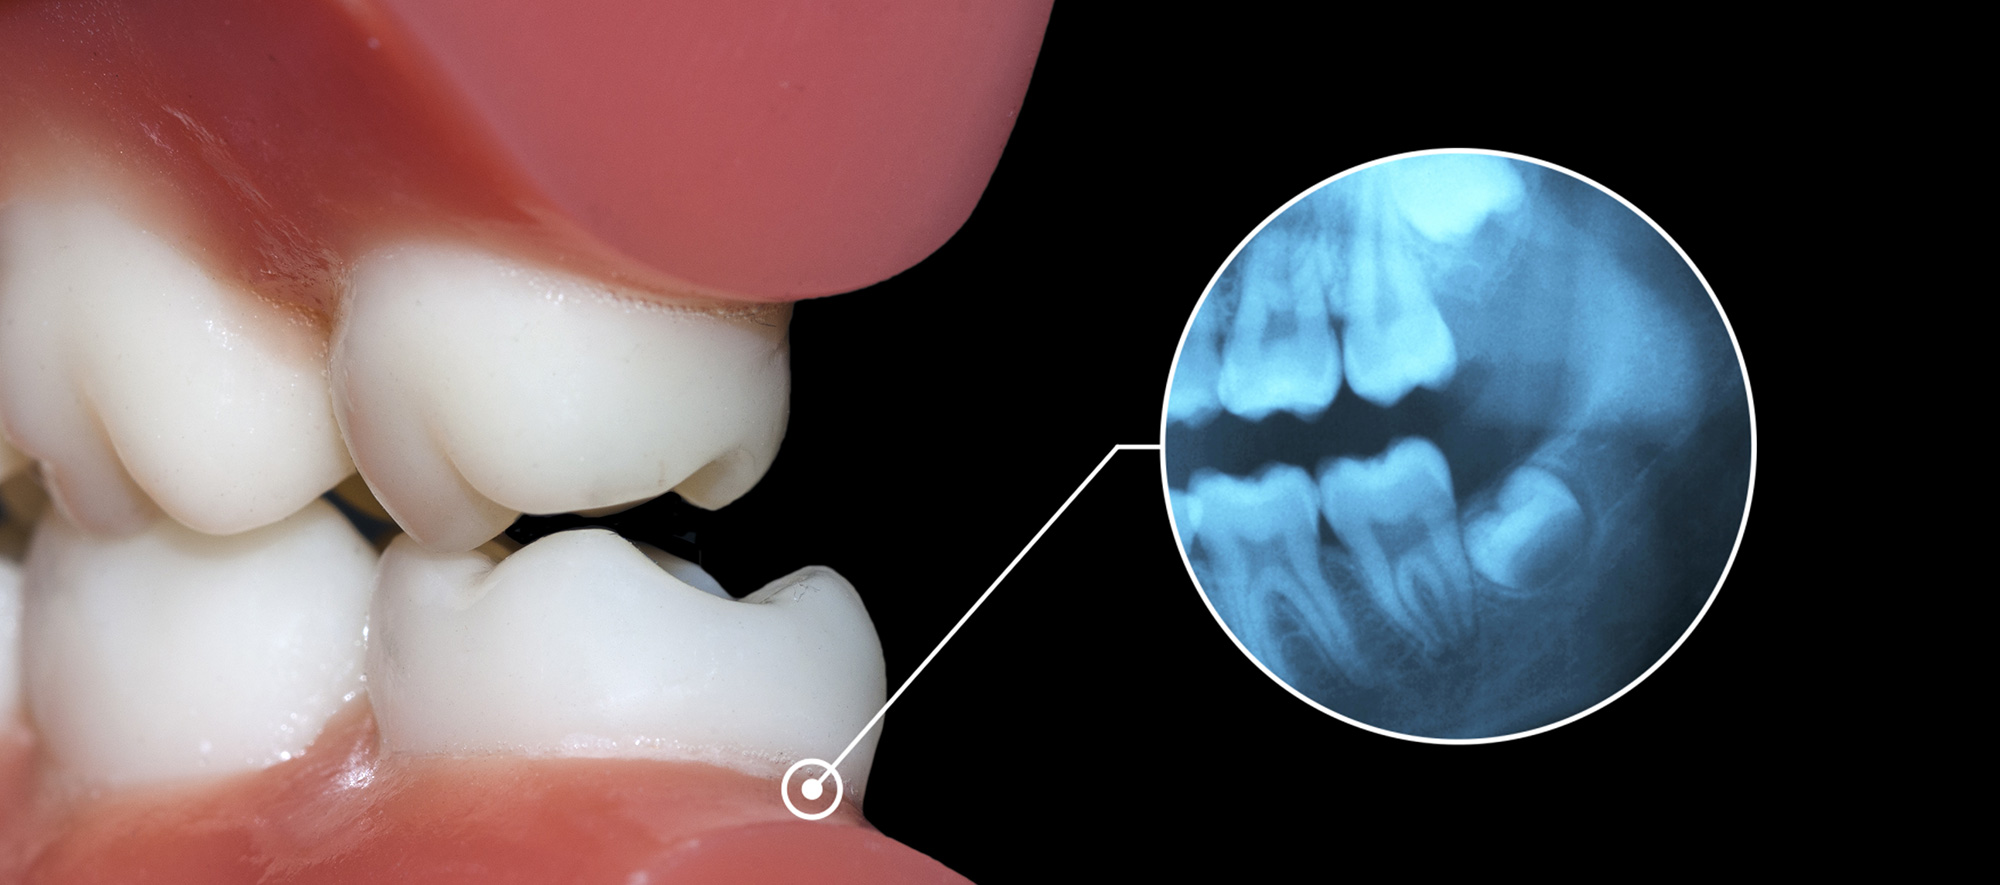

A oclusão dentária exerce influência direta sobre a função mastigatória, a estabilidade do tratamento ortodôntico e a saúde do sistema estomatognático como um todo. Na prática

A dor na região posterior da mandíbula, associada à dificuldade de mastigação e limitação de abertura bucal, é um cenário recorrente na rotina clínica. Em muitos